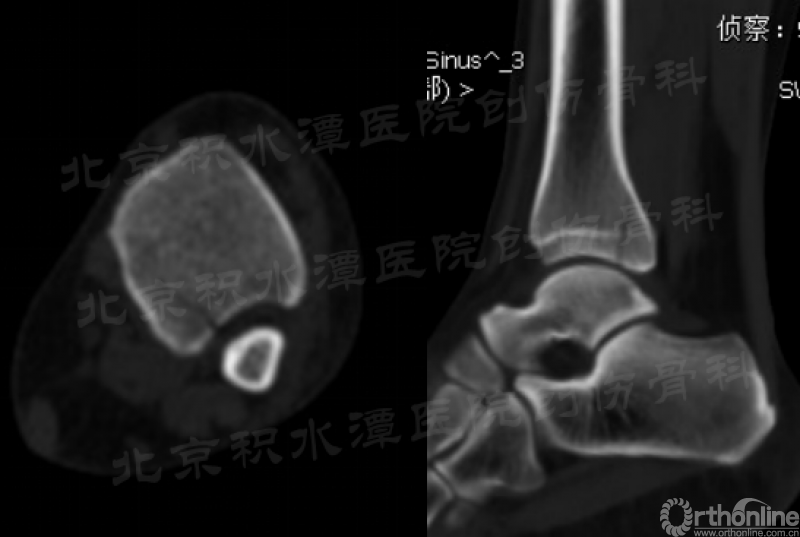

急诊常规拍摄X片:踝关节正侧位X线片无明显异常;但踝关节(或足)斜位可见后踝骨折无移位(不明显)。

复查CT可见后踝骨折无移位(猜测当时踝关节处于跖屈位,制动电动车使左踝受到轴向应力),胫腓骨正侧位带膝未见腓骨近端骨折。

对于以上这例病例,这种骨折类型也不是常见的踝关节骨折类型,若是没有很仔细的查体和阅片,很容易发生漏诊。